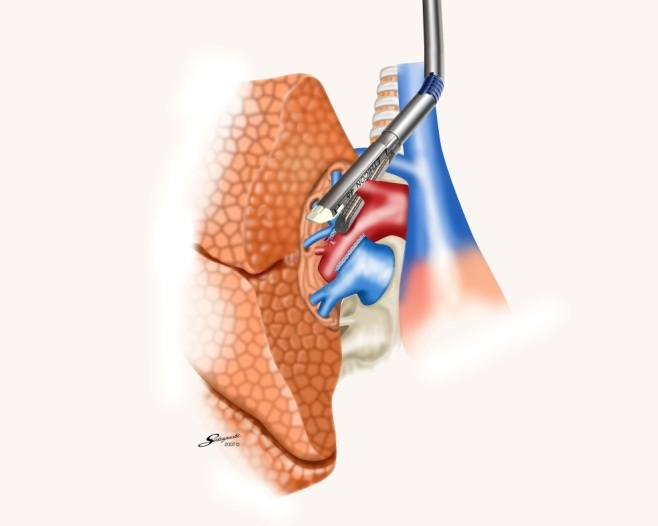

胸腔鏡手術の実際(右肺上葉切除時の自動縫合器使用例)

肺静脈切離

肺動脈切離

気管支切離

葉間切離

術中に使用しているデバイス

自動縫合器

カートリッジの仕組み